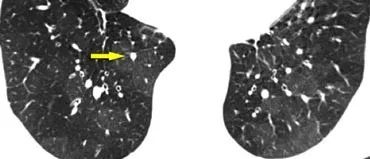

下图,我们看到实变和GGO持续存在和体重减轻,没有感染的迹象。

这表明这是一种慢性疾病。

没有蜂窝状或牵张性支气管扩张,所以我们可以排除纤维化。

体重减轻暗示着一种恶性疾病。

组织学检查显示支气管肺泡细胞癌。